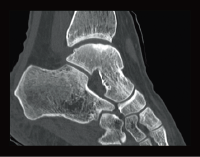

Клинические изображения

Специальная программа HIMAR для подавления влияния на изображения включений с большим КТ числом даёт возможность визуализировать области и ткани, прилежащие к металлическим объектам, например имплантам.